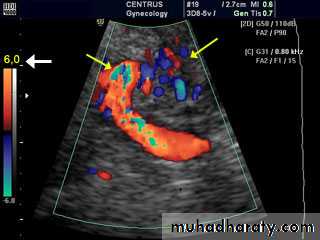

Doppler

Duplex in varicose veins